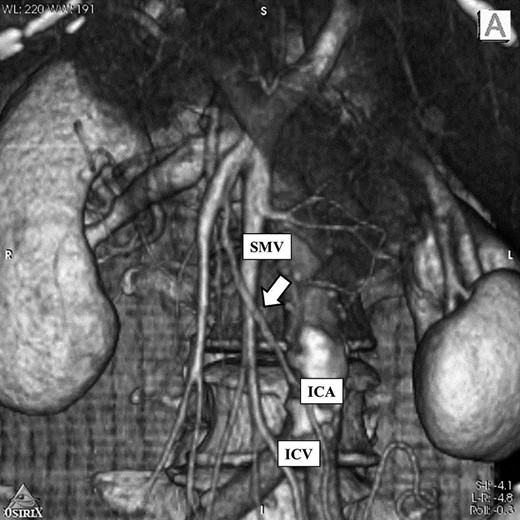

Abdominal CT scan showed complete inversion of the internal organs. 3D-CT angiography revealed no right colic artery and ileocolic artery was located ventral to superior mesenteric vein, and there was angioplany with the exception of mirror image (Fig. 2). Barium enema revealed an elevated lesion in the ascending colon (Fig. 3). Colonoscopy revealed an ulcerative tumor in the adjacent ileocecal valve of the ascending colon; biopsy confirmed that it was a well-differentiated adenocarcinoma. A laparoscopic right colectomy with radical lymphadectomy was performed by ambidextrous surgeon. Under general anesthesia with the patient in a modified lithotomy position, the operator and endoscopist were situated on the right, the first assistant was on the left, the reverse of the locations for orthotopic patients. Trocars also were placed in a mirror image manner, including a 12-mm umbilical trocar for camera, a 11-mm trocar in the right lower quadrant of the abdomen as working port for the operator, 5-mm trocars in the right upper, left upper and left lower quadrant of the abdomen (Fig. 4). The liver was located on the left and the spleen on the right. There was severe adhesion of sigmoid colon and mesentery of terminal ileum to the retroperitoneum. The duodenum had weak fixation to the retroperitoneum and malrotation (Fig. 5). The laparoscopic procedure was commenced breaking up the adhesion of sigmoid colon and mesentery of terminal ileum and retroperitonium. It took almost 40 minutes to break up. We then incised the peritoneal reflection of the terminal ileum to make a tunnel between the mesocolon and retroperitneum until the second portion of the duodenum and head of the pancreas were seen. The ileocolic vessels were identified and divided after the superior mesenteric vein exposed. Dissection of the lymph node started from ileocolic vessels and continued up of the root of surgical trunk (Fig. 6). Next, the remaining ascending colon was fully mobilized along Toldt’s fascia medially to laterally. By extending the 12-mm trocar of the umbilicus, on approximately 40-mm long vertical incision was made, through which we carried the ascending colon include the tumor out. Functional end-to-end anastomosis between the ileum and the transvers colon was extracorporeally performed using staple. No additional port was needed. Operation time was 237 min and the blood loss were 20 ml. Macroscopically, the tumor was a 40 × 40 mm ulcerated lesion in the adjacent ileocecal valve of the ascending colon. Histological examination of the resected specimen disclosed well-differentiated adenocarcinoma. Lymph node metastasis was found in 2 out of 11 nodes (StageIIIB: T3, N1, M0). The patient was discharged on the 12nd day after the operation, without any complication.

3D-CT image: There was no right colic artery and ileocolic artery was located ventral to superior mesenteric vein (arrow). And there was angioplany. SMV: Superior mesenteric vein ICA: Ileocecal artery ICV: Ileocecal vein.